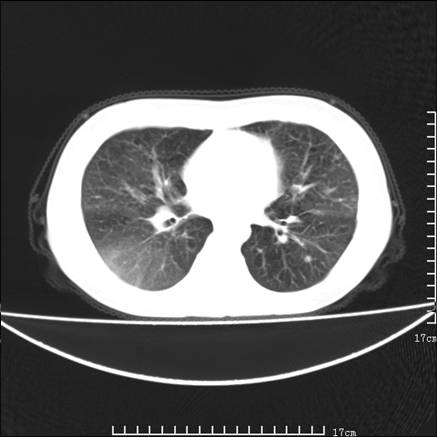

女,46岁,患胃溃疡多年,溃疡大小约1.0cm左右,后于5年前手术,病理为胃癌。主诉:半月前感冒后胸闷,气短,有咳嗽,无明显咳痰,无发热。偶有腰背部不适。

以下为高分辨扫描图像

肺癌性淋巴管炎征象分为主要征象及合并征象,主要征象包括:

1、近肺门支气管血管周围间质结节状增厚;

2、小叶间隔结节状增厚;

3、小叶中央间质结节状增厚;

4、胸膜下间质结节状增厚。

合并征象为:纵隔淋巴结增大,胸腔积液,肺多发随机分布的小结节等。